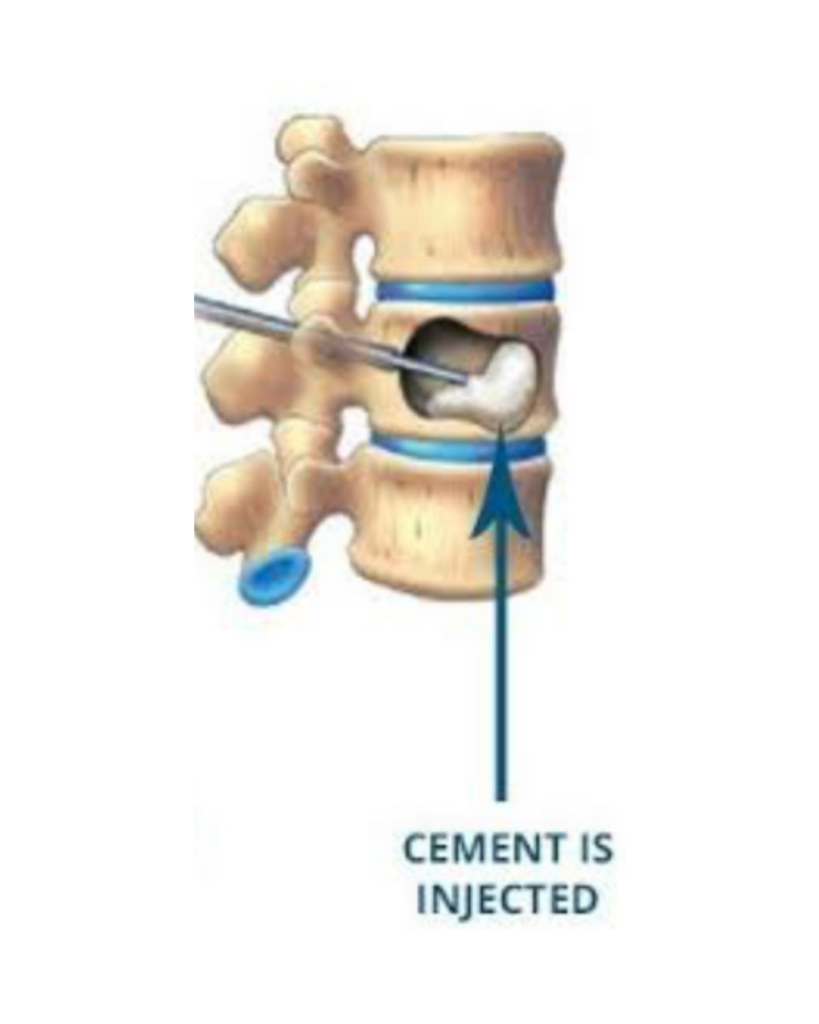

A minimally invasive vertebral cement augmentation (Kyphoplasty) was performed under local anaesthesia, providing :

A minimally invasive kyphoplasty performed under local anaesthesia provided safe and immediate pain relief, restoring mobility without exposing the patient to the risks of major surgery. This case highlights how interventional pain medicine can offer transformative outcomes even when surgical options are limited, reaffirming that restoring function and dignity is possible through thoughtful, multidisciplinary collaboration.